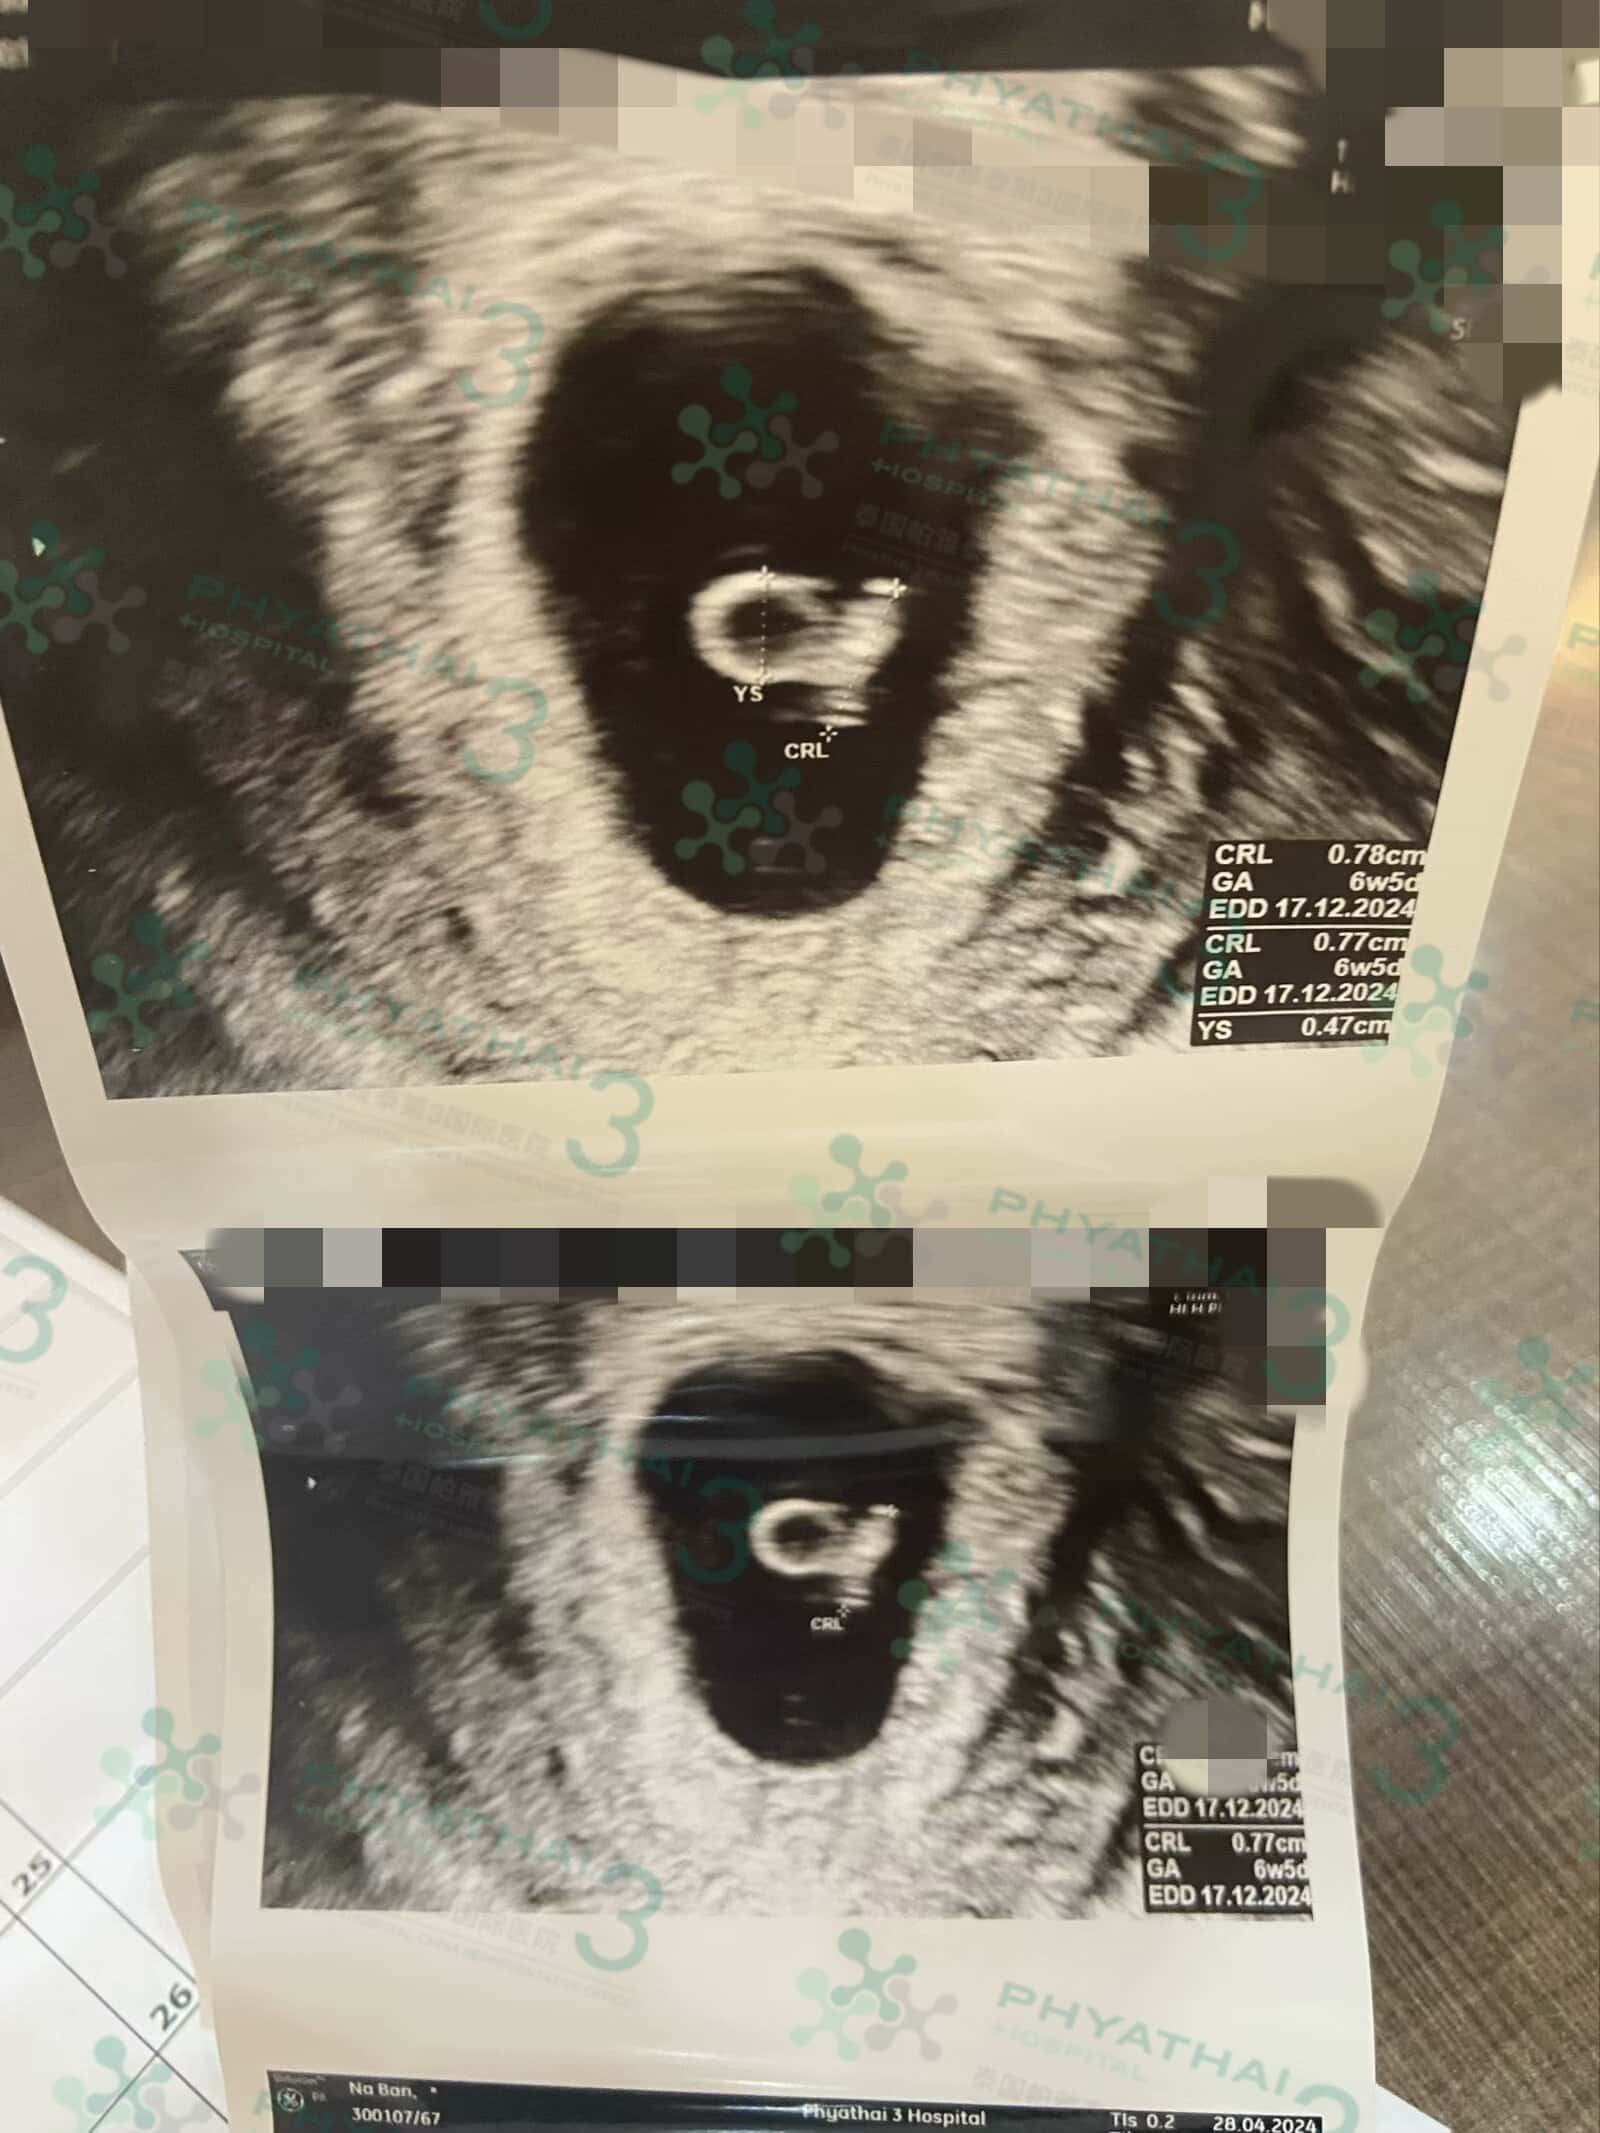

看到孕囊了耶 好奇妙呀

看到孕囊了耶 好奇妙呀以前不明白为什么准妈妈去产检大部分会盯着阴超报告看半天 今天和好孕家庭一起听到了宝宝的胎心 咚咚咚的实在是太悦耳啦 听到感动 希望宝宝和宝妈能够健健康康顺顺利利的